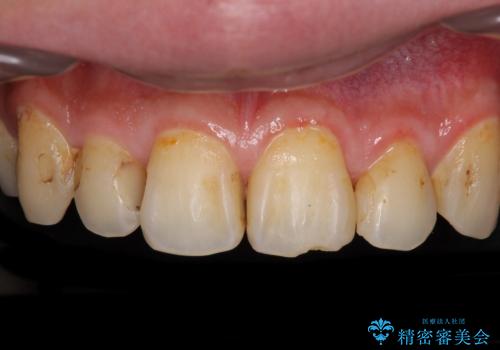

- 以前矯正を行った際に前歯が虫歯だらけとなり、審美面を気にして来院された患者様です。

虫歯の大きかった左右犬歯はオールセラミッククラウンで補綴治療をおこない、4前歯は研磨や古い充填物の詰め直しを行いました。